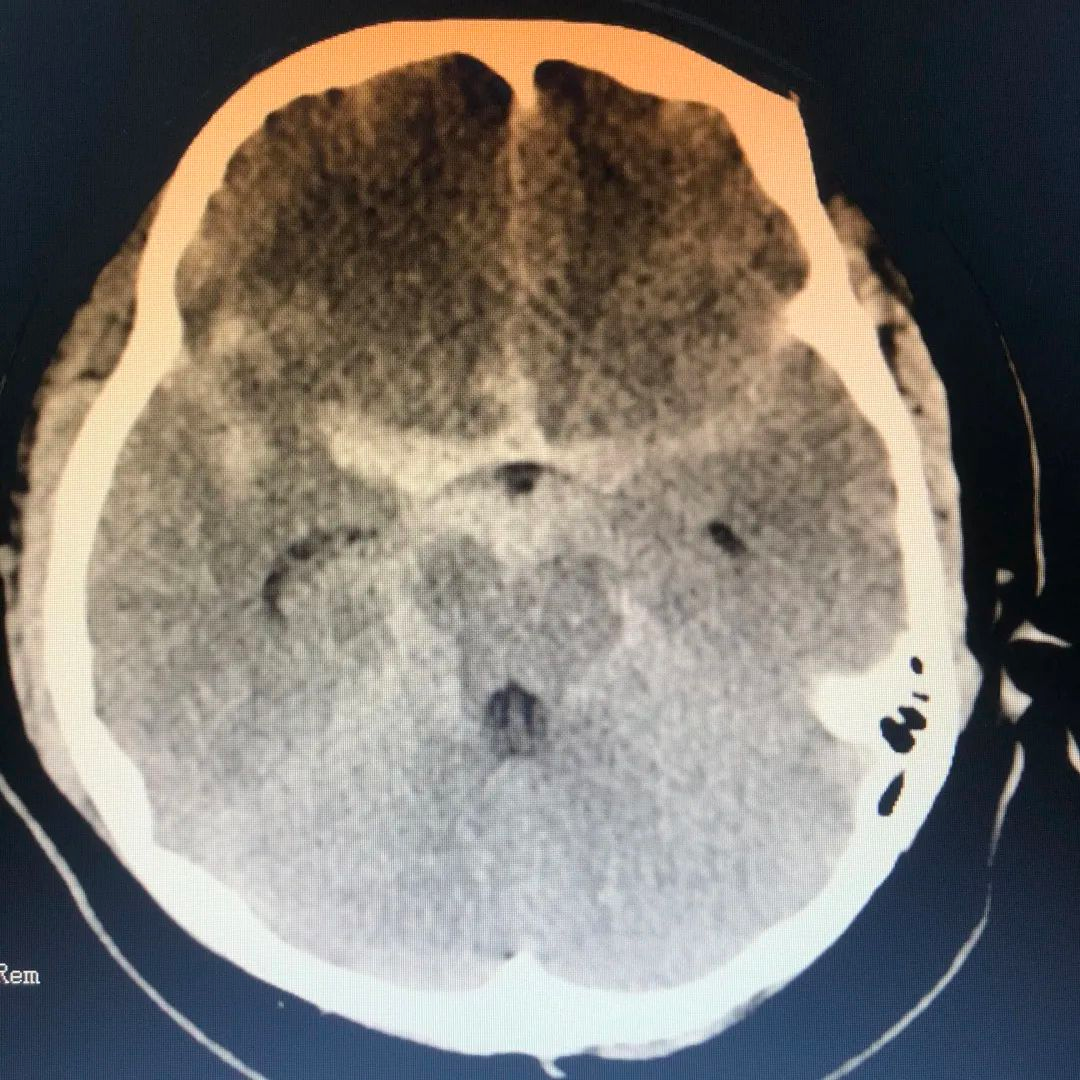

头颅CTA显示“蛛网膜下腔出血,右侧颈内C7段瘤样扩张”

CT造影